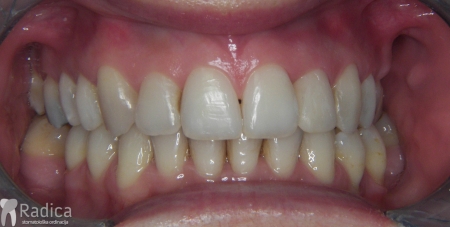

Slučaj 3: ispravljanje kompresije Invisalign full terapijom